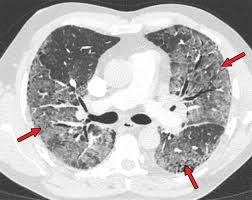

Entropy Free Full Text Classification Of Covid 19 Coronavirus Pneumonia And Healthy Lungs In Ct Scans Using Q Deformed Entropy And Deep Learning Features Html

Entropy Free Full Text Classification Of Covid 19 Coronavirus Pneumonia And Healthy Lungs In Ct Scans Using Q Deformed Entropy And Deep Learning Features Html from www.mdpi.com